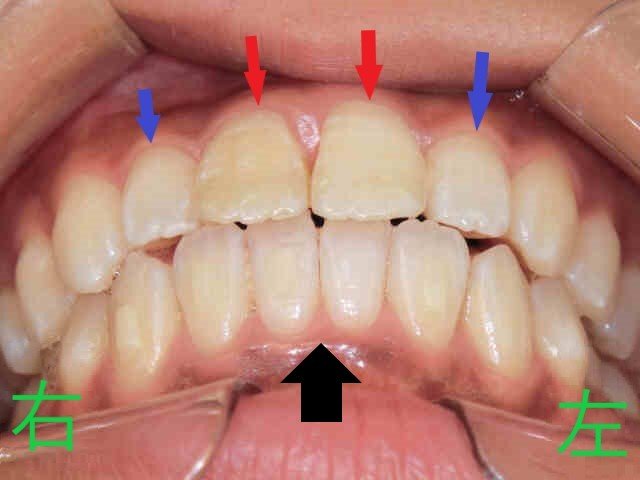

左の写真は、矯正治療開始から3か月後の上顎の様子です。上顎左右中切歯の前突感が緩和され、左右側切歯が内側から外側へと移動しつつあることが確認できます。

右の写真は上下の噛み合わせを下から見上げたもので、下顎前歯が内側に移動し、それに伴い上顎中切歯も内側に移動。前突感の軽減が明瞭です。側切歯の外側移動も進行中ですが、改善の余地が残ります。

治療経過の写真(3か月後)では、上顎と下顎の歯列が適切な位置に配列されつつある様子が見られます。下顎前歯が後方に移動した分、上顎前歯の前突も解消されつつある状態です。